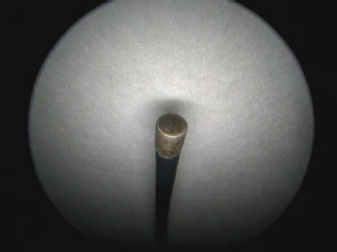

One-and-a-half month after the diagnosis, surgery using monopolar electrocautery was performed. For that, we only needed a semirigid Karl Storz monopolar coagulating ball electrode (3 Fr × 53 cm), LED Surtron 120 high-frequency electrosurgery unit in a monopolar mode, and a grounding steel plate prepared with a thick ultrasonographic gel layer in contact with shaved patient’s skin (Figs. 3-5).

Fig. 4. Semirigid Karl Storz monopolar coagulating ball electrode (3 Fr × 53 cm) connected to a monopolar 4 mm Ø HF connection cable.

Fig. 5. A semirigid Karl Storz monopolar coagulating ball electrode tip.